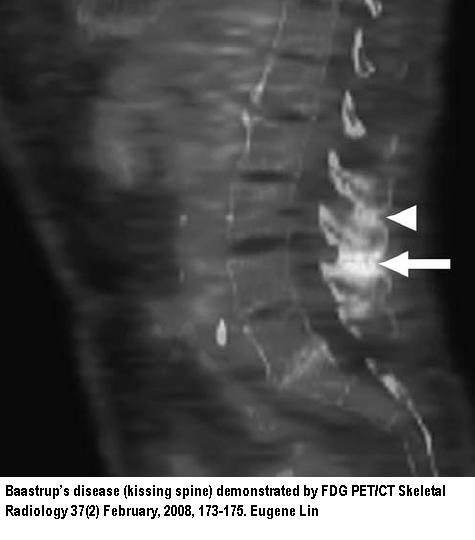

PET - CT showed it beautifully abstract here

- Called "kissing-spine" disease the impingement of 2 spinoud process vertebra can cause problems.